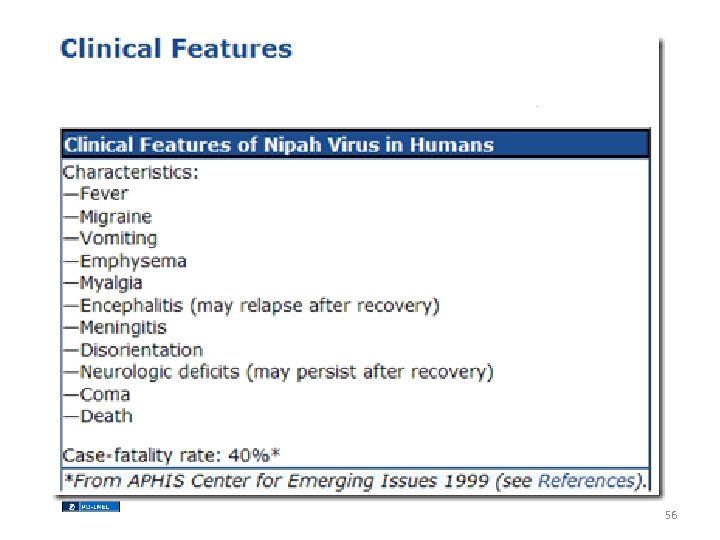

Henipah(Nipah) Virus Encephalitis • • 1998 - 1999 Malaysian pig farmers and health care workers 200 cases Transmission – Secretions from pigs, fruit bats – Human to human? – CDC • Bangladesh Bans Sale of Palm Sap After an Unusually Lethal Outbreak – New York Times DONALD G. Mc. NEIL Jr. Published: March 21, 2011 54

56